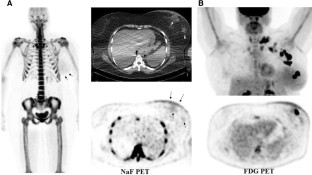

NaF positron emission tomography/computed tomography (PET/CT) images of 69 newly diagnosed breast cancer patients were reviewed. F-18 fluoride uptake as maximum standardized uptake value (NaF SUVmax) was measured in the primary tumor, enlarged axillary lymph nodes and contralateral normal/non-tumoral breast tissue. Low-dose CT images were reviewed to locate the primary tumor and grossly assess its calcification and check for ipsilateral axillary lymphadenopathy. Whole body NaF PET/CT images were reviewed to search for bone metastases. Eighteen patients also underwent F-18 fluorodeoxyglucose (FDG) PET/CT study.

Results

The primary breast tumor was clearly seen as focal or diffuse uptake on NaF PET images in 27 of 69 patients (39%) (mean NaF SUVmax: 2.0 ± 1.0). In the rest, there was only mild bilateral diffuse breast uptake. When analyzing images per histological subtype (42 patients, 43 tumors), 14 of 31 invasive ductal carcinomas (IDC) (45%) and 3 of 4 ductal carcinoma in situ (DCIS) were visible on PET. Five invasive lobular carcinomas, 2 invasive mammary carcinomas, and 1 mucinous carcinoma were not visible on PET. Mean NaF SUVmax of contralateral normal/non-tumoral breast tissue was 1.0 ± 0.4. There was no significant difference in mean NaF SUVmax of primary tumor in cases with and without calcification or with and without axillary lymphadenopathy (p 0.892 and 0.957). There was no correlation between NaF SUVmax and FDG SUVmax values of the primary tumors (r 0.072, p 0.797, Pearson correlation).